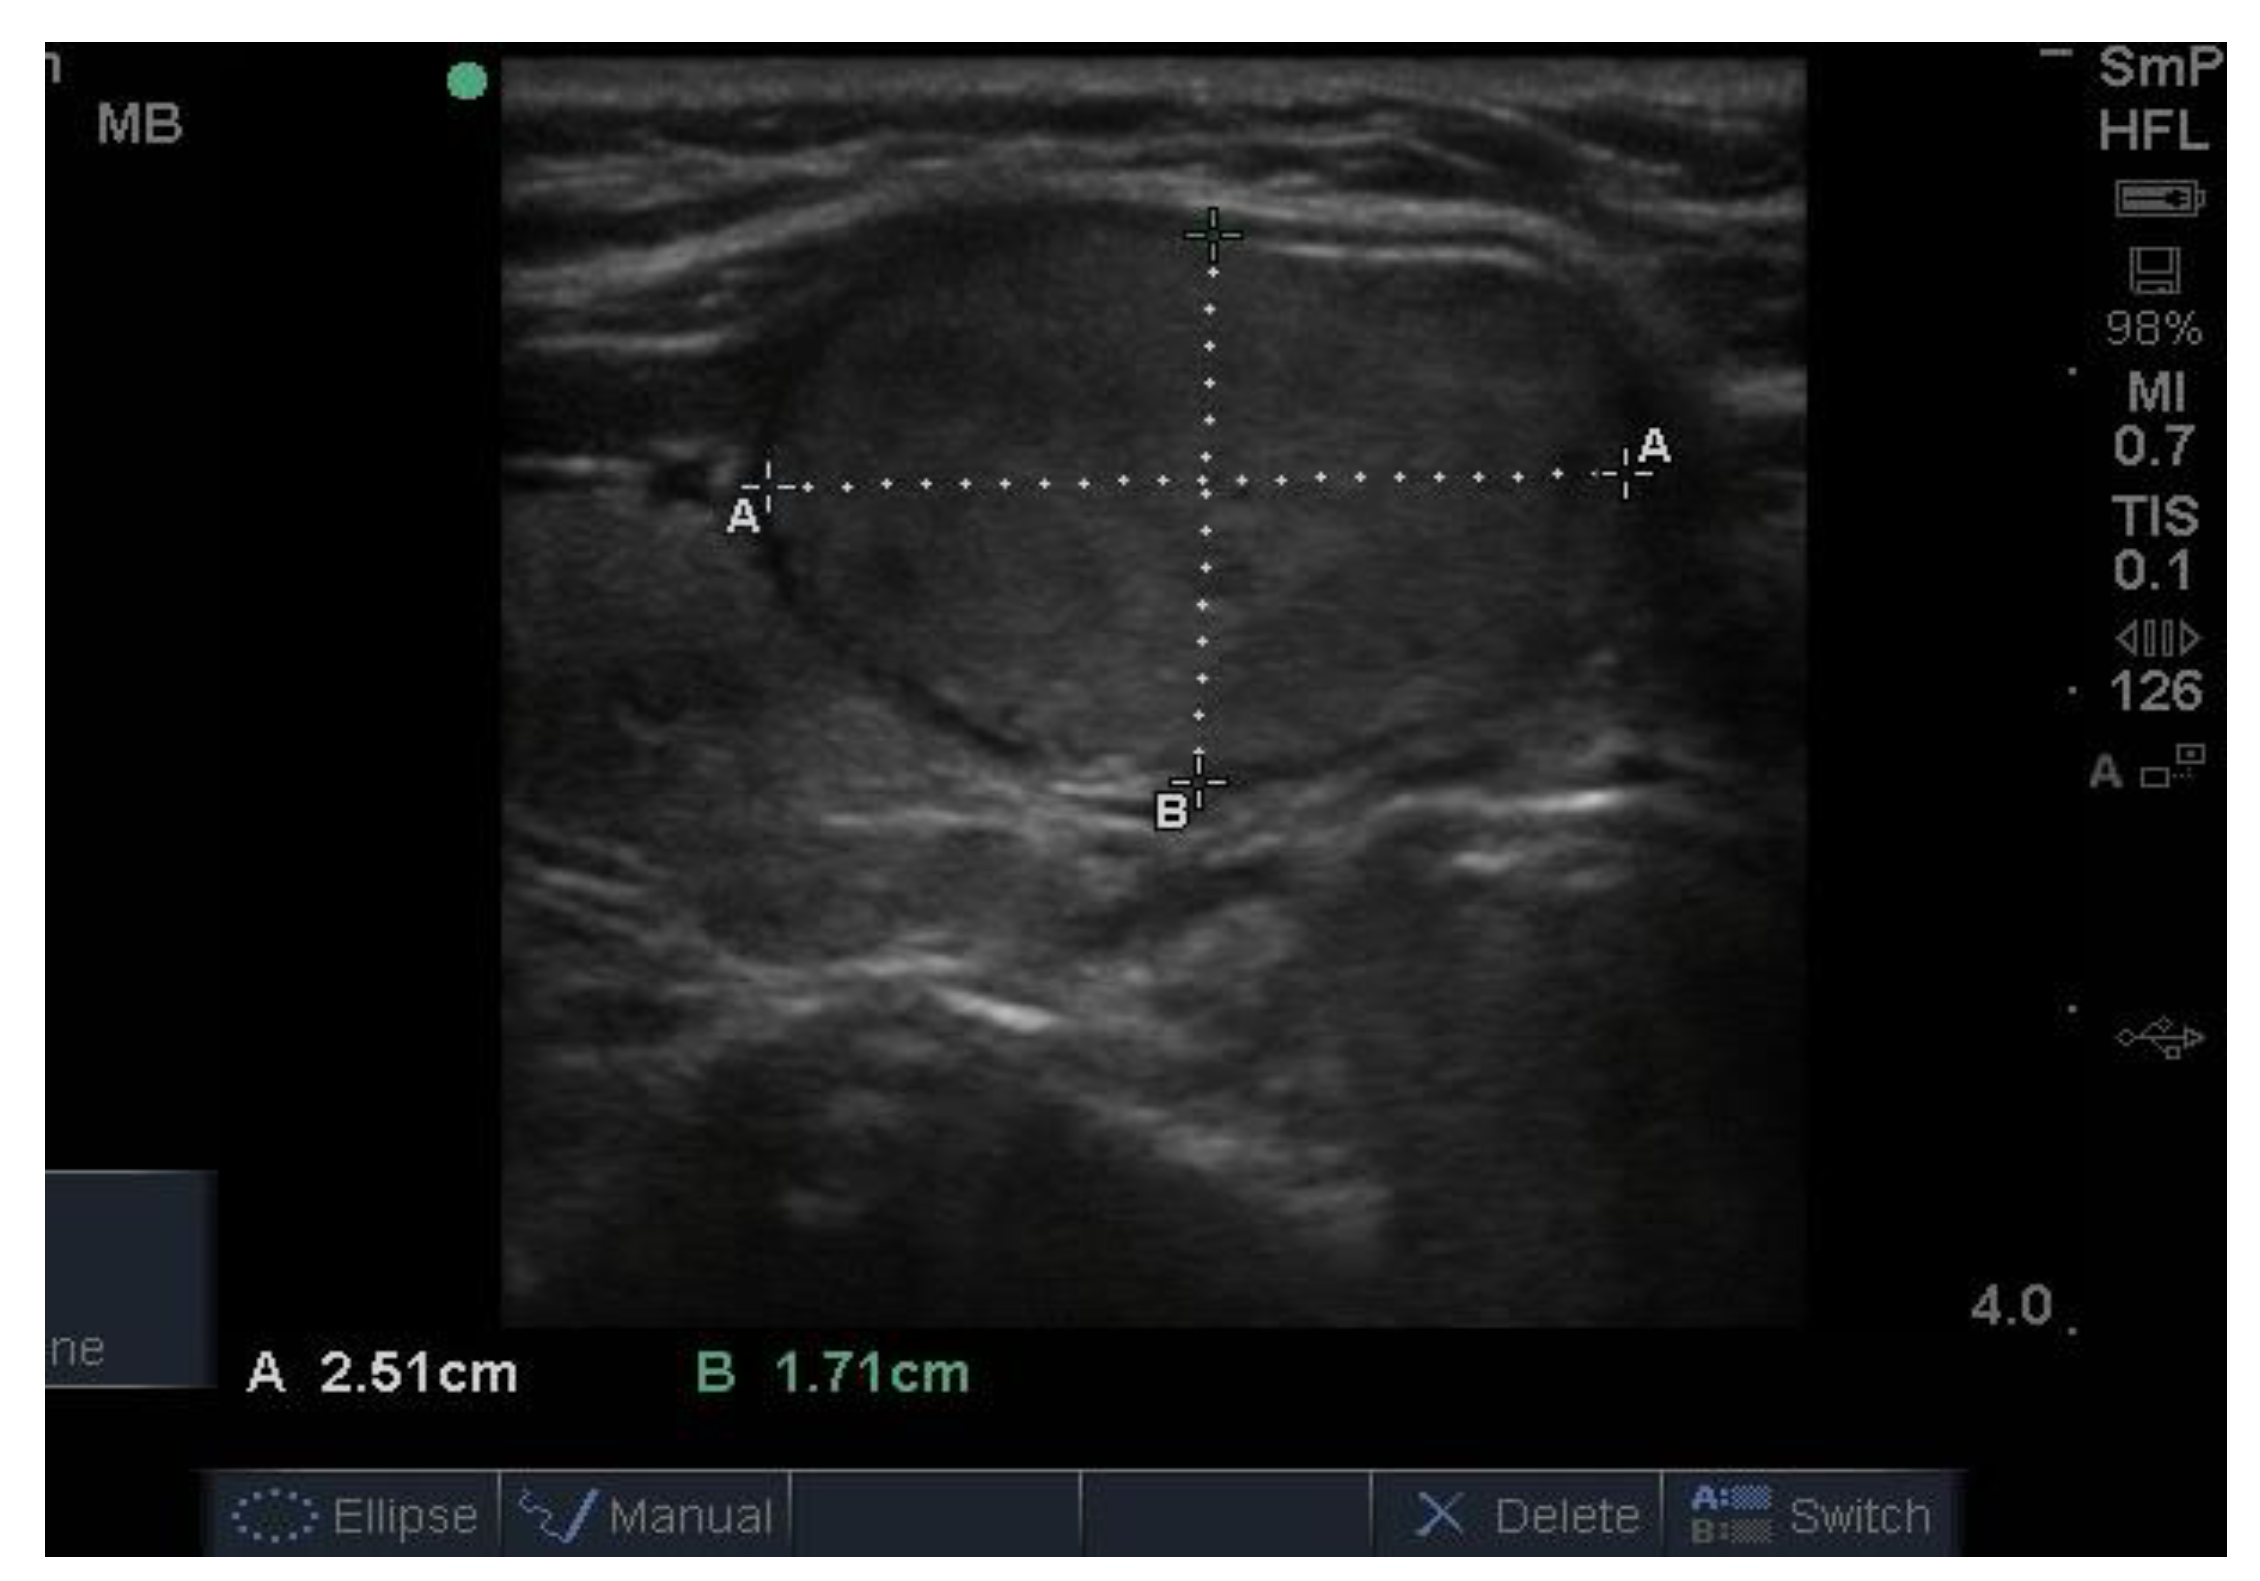

Follicular nodules are much less common than colloid nodules with a different appearance on ultrasound; they are more cellular, giving a solid appearance, with a whitish colour, i.e., less hypoechoic. They too have a sharp edge and halo and grow slowly over time [5]. The problem with these lesions is that FNAB is unable to differentiate between a benign follicular adenoma and follicular cancer, and if the latter is suspected, thyroid surgery is the final arbitrator. About 10% of benign thyroid nodules are follicular, and most of them end up being removed. Two examples of follicular nodules that were finally proven to be benign are shown in Figure 4. On follow-up ultrasound (US), 6–12 months later, repeat biopsy might be indicated if a nodule has grown by 20% or more in two or more dimensions; benign nodules also grow, but less quickly.

Figure 4.

Two examples of follicular nodules that were shown at surgery to be benign. The nodules are roughly oval shaped, slightly hyper echoic and have sharp edges and, particularly, the bigger of the two, thick halos.